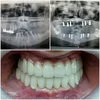

Zirkonyum uygulamalar

Implant tedavisi

Porselen uygulamaları